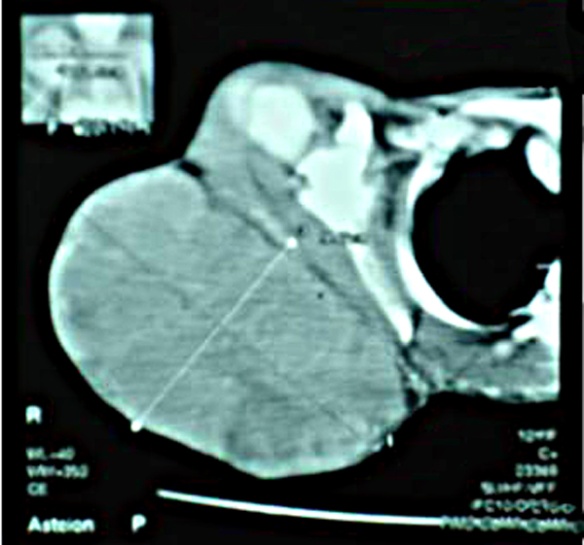

phosphatase were within normal limits. X-ray and CT scan of the scapular region

showed soft tissue swelling without any bony involvement (Fig. 2,3). Fine needle aspiration suggested malignant soft tissue tumour. Incisional biopsy confirmed the diagnosis of ES. The

Figure 2:

CT scout view showing soft tissue shadow

Figure 3:

CT scan showing soft tissue tumour

of X-ray and CT scan of our case showed the tumour as

soft tissue swelling over scapular region. Molecular and cytogenetic analysis